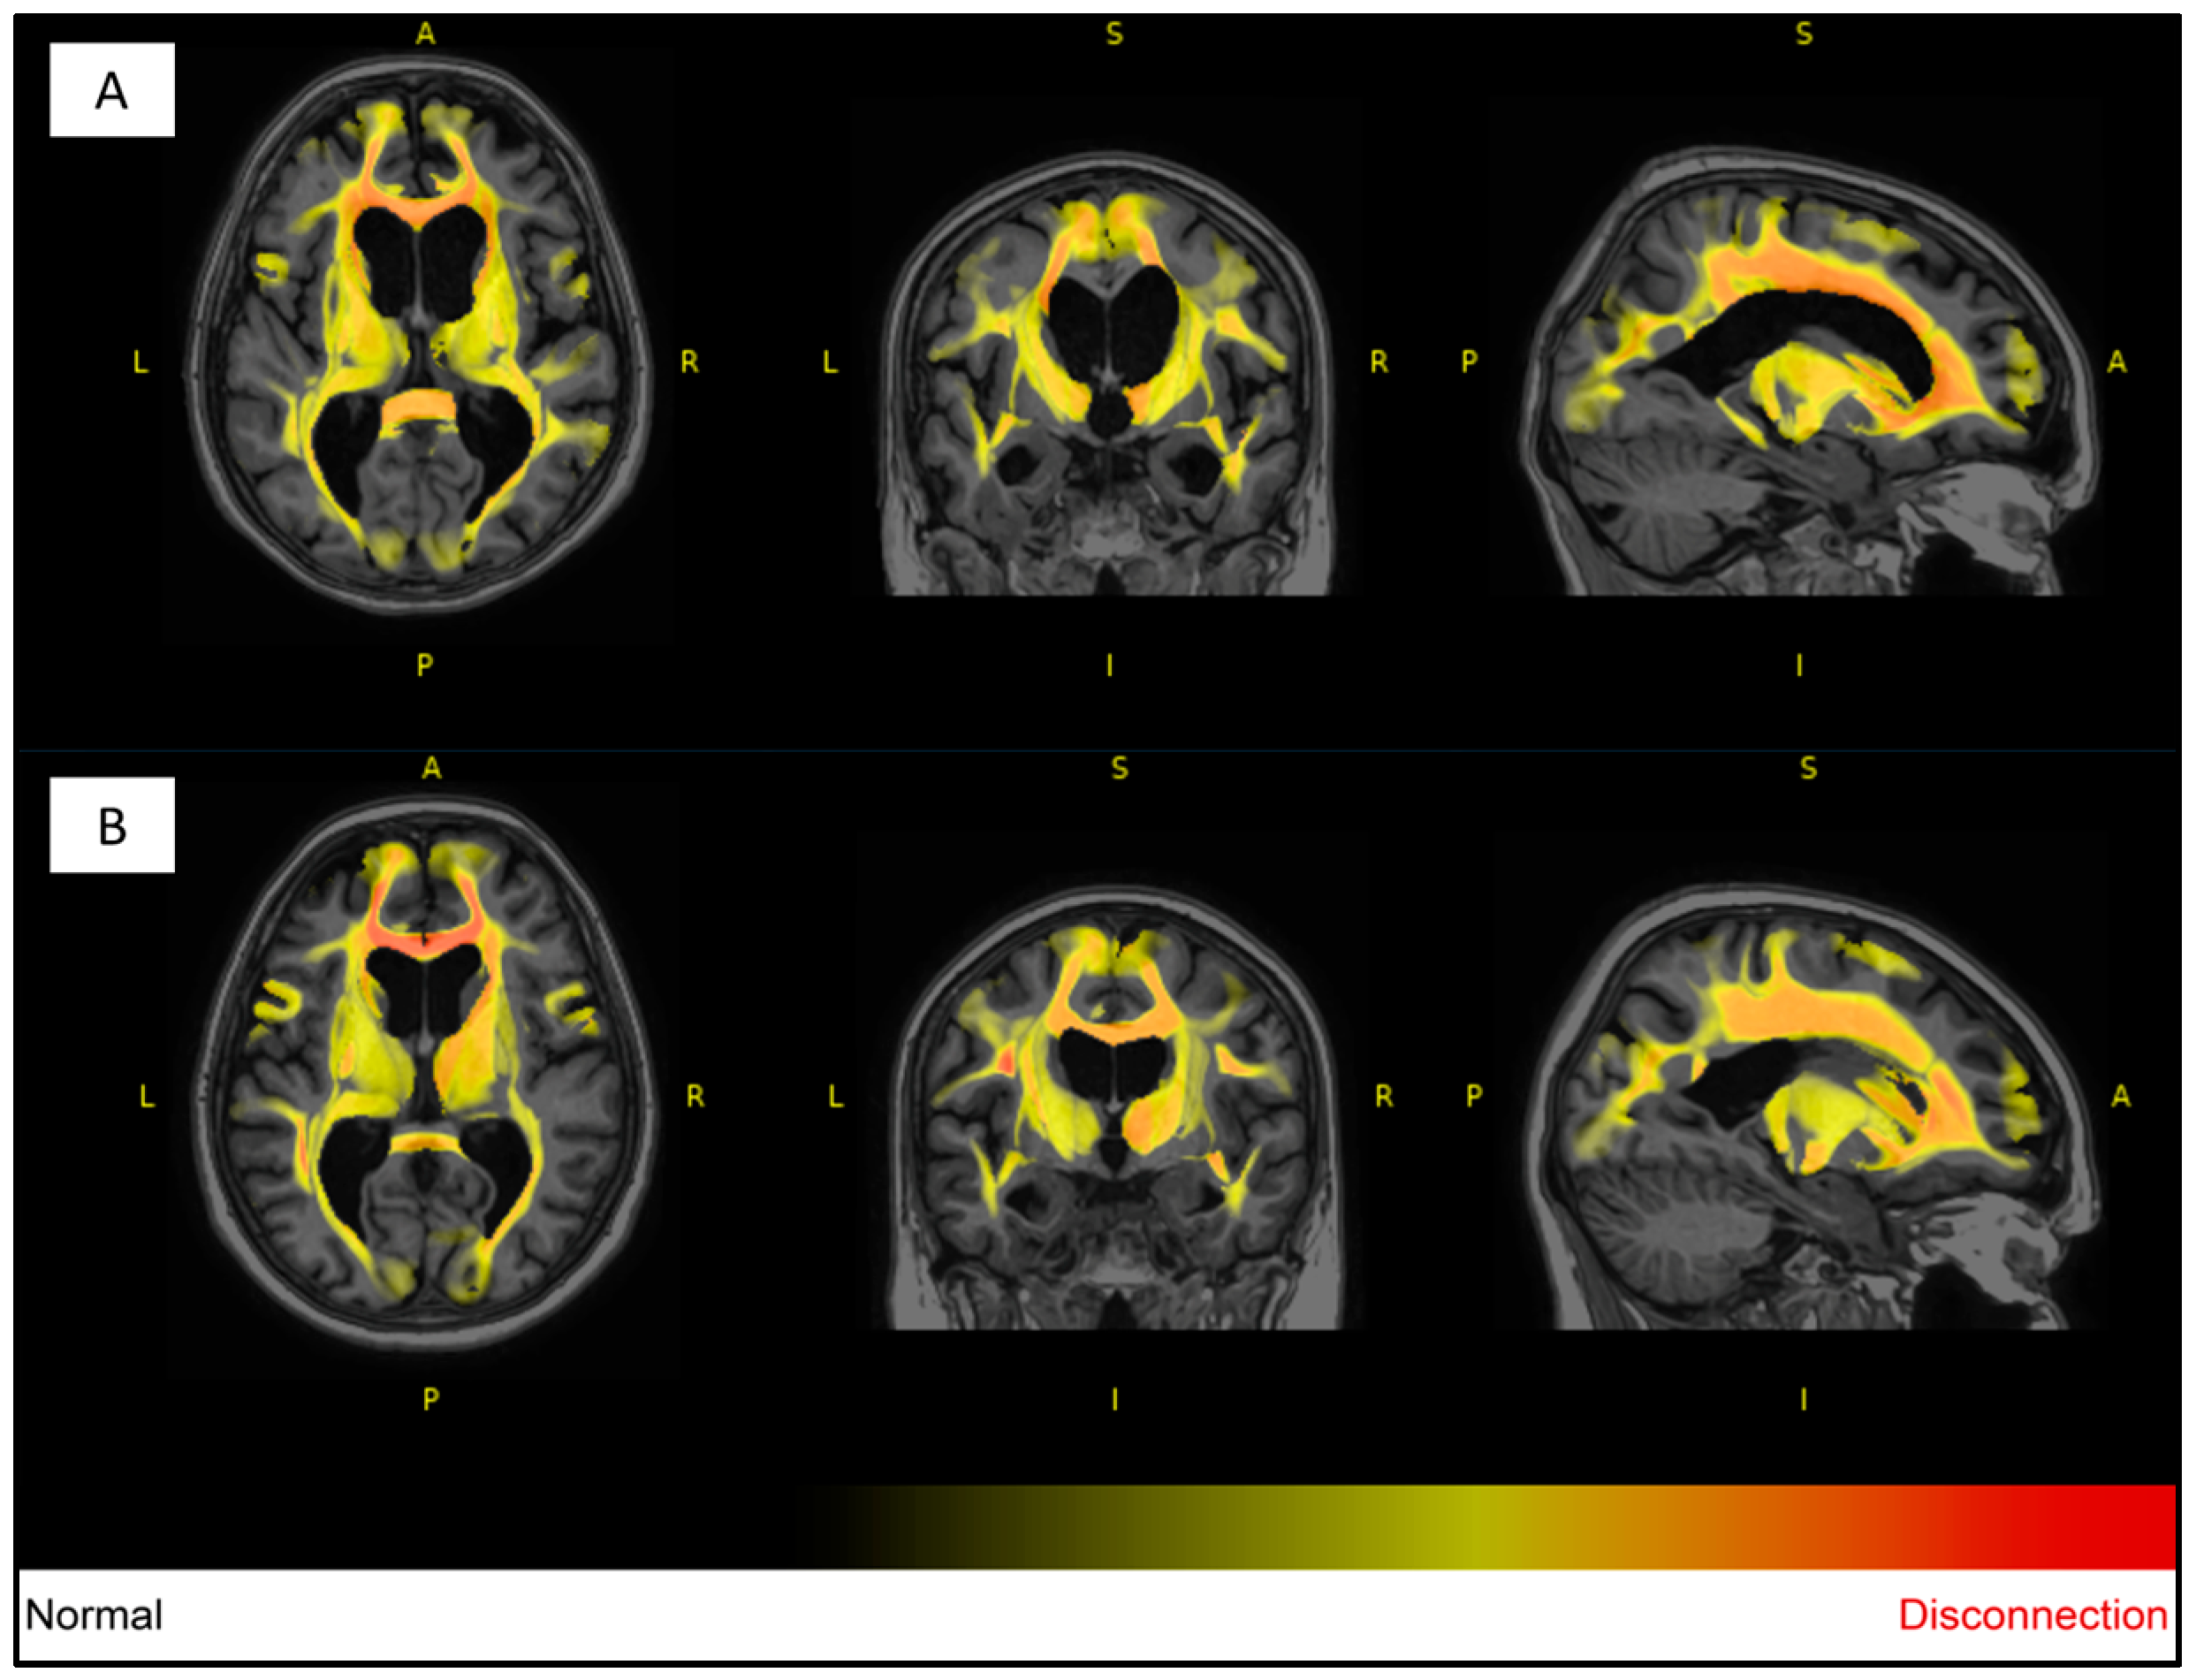

| Variable | Unaffected Twin | Affected Twin |

|---|---|---|

| Total lesions count | 24 | 36 |

| Total lesions volume (cm3) | 3.9192 | 30.0650 |

| Periventricular lesions count | 9 | 8 |

| Periventricular lesions volume (cm3) | 3.3902 | 29.4052 |

| Deep white lesions count | 12 | 17 |

| Deep white lesions volume (cm3) | 0.3136 | 0.3823 |

| Juxtacortical lesions count | 2 | 8 |

| Juxtacortical lesions volume (cm3) | 0.0362 | 0.2238 |

| Infratentorial cerebellar lesions count | 1 | 2 |

| Infratentorial cerebellar lesions volume (cm3) | 0.1793 | 0.0403 |

| Infratentorial medullary lesions count | 0 | 1 |

| Infratentorial medullary lesions volume (cm3) | 0 | 0.0132 |

| Volumes | Unaffected Twin | Affected Twin |

| Total white matter volume (cm3) | 403.59 | 387.12 |

| Total gray matter volume (cm3) | 664.13 | 623.45 |

| Total brainstem volume (cm3) | 20.34 | 16.14 |

| Frontal lobe volume (cm3) | 168.08 | 155.58 |

| Temporal lobe volume (cm3) | 103.83 | 103.51 |

| Parietal lobe volume (cm3) | 97.28 | 89.20 |

| Occipital lobe volume (cm3) | 80.16 | 76.79 |

| CSF Volume | Unaffected Twin | Affected Twin |

| Total CSF volume (cm3) | 220.89 | 272.12 |

| Inferior lateral ventricle volume (cm3) | 4 | 7.30 |

| Lateral ventricle volume (cm3) | 64.49 | 94.48 |

| 3rd ventricle volume (cm3) | 2.93 | 3.85 |

| 4th ventricle volume (cm3) | 3.55 | 5.27 |

| External CSF volume (cm3) | 145.92 | 161.23 |